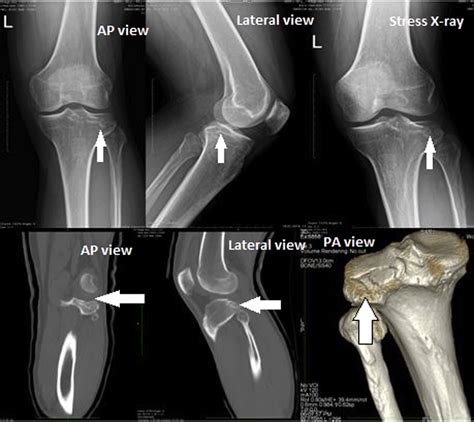

• Tibial Plateau Fractures: These are typically caused by high-energy trauma, such as car accidents or falls from heights. A fracture here disrupts the smooth cartilage surface, potentially leading to post-traumatic arthritis.

To evaluate the medial tibial plateau, orthopedic specialists utilize a combination of clinical examinations and diagnostic imaging. Because the knee joint is surrounded by soft tissues, X-rays alone may not reveal the full extent of an injury.

X-ray Best for identifying fractures, major bone displacement, and joint space narrowing.

MRI Essential for viewing soft tissues, cartilage defects, and bone marrow edema.

CT Scan Provides detailed 3D mapping of complex or comminuted fractures for surgical planning.